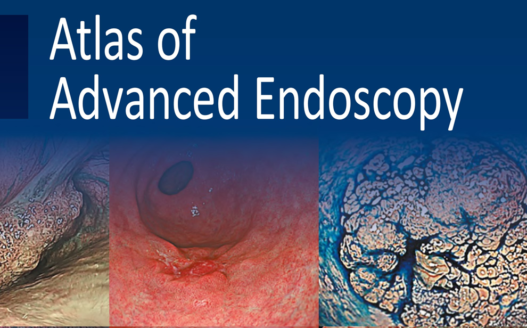

Since the introduction of this classification, several IEE techniques have become commercially available through advances in endoscopy technology, including blue light imaging (BLI), linked color imaging (LCI), red dichromatic imaging (RDI), and texture and color enhancement imaging (TXI). Therefore, a revised version including those techniques is presented in Fig. 1.

The LASEREO system (FUJIFILM Co., Tokyo, Japan) based on laser endoscopy was developed for advanced IEE, including WLI, BLI, and LCI. LCI using short-wavelength narrow band laser light combined with white laser light is a new technique that enhances differences in red coloration through digital processing [2]. This enables LCI to visualize red lesions better by enhancing their intensity relative to whitish lesions, which appear whiter. Recently, a controlled, multicenter trial with randomization using minimization has reported that LCI is more effective than WLI for detecting neoplastic lesions in the pharynx, esophagus, and stomach [3].